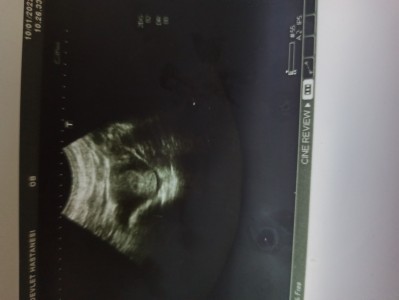

Kese de bebek var mı bir bakar mısınız doktor kalp atışı için haftaya gel dedi 5+6 haftalık hamileyim

Gebelik haftası 5+6

Kesen cok küçük canım haftaya bebek görülür kalp atışını 8. Haftada duyarsınız endişelenme bende de öyle olmuştu

Daha çok küçükmüş haftaya görürsünüz. Biz de önce keseyi sonraki hafta bebeği gördük. Sıkıntı yapmayın :)